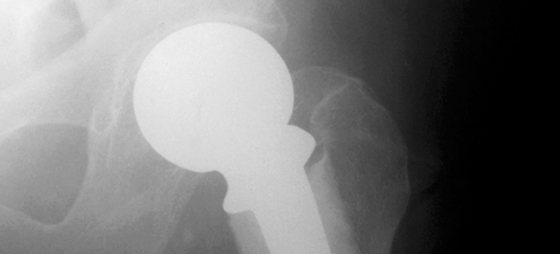

Tack för bra information om höftsmärta. Jag fick en protes för tre månader sedan. På sjukhuset gav läkaren mig ett träningsschema som han bad mig följa. Det viktigaste är att ligga på rygg och lyfta benen upp i luften. Kryckorna skulle jag sluta med efter 8 veckor. Det är den informationen läkaren gav mig och som jag har följt. Efter ca 10-15 minuter får jag ont och börjar halta. Vad ska jag göra?

Du har naturligtvis haft ditt höftproblem en längre tid, kanske flera år innan du valde en protes. Följaktligen har du utvecklat förkortad muskelatur speciellt i ljumsken – höftbenen. Det resulterar bl a i att dina sätesmuskler blir hämmade och svagare.

De svaga musklerna måste stärkas och de korta töjas ut för att skapa en ny balans.

Efter en operation tar det normalt från en vecka upp till en månad innan du känner att du kan belasta den opererade höften full ut. Tiden det tar varierar som du förstår, så därför kan egentligen ingen utom du själv bedöma när det är dags att kasta kryckorna. Du ska inte ha smärtor när du går. Går du en längre sträcka kan du eventuellt känna att en krycka är att föredra. Det är med andra ord en avgörande betydelse att du är ärlig mot dig själv. Du tjänar ingenting på att provocera smärtan.

Kan du inte hålla balansen när du står på det opererade benet i minst 10 sekunder utan att stötta dig mot något och utan smärta ska du fortsätt att använda krycka.

Det bästa är att du får en bedömning av en fysioterapeut och adekvat träning. Det ger bättre och snabbare reslutat. Har en överbelastning uppståt finns det en orsak till detta. Avlastning och behandling kommer då att vara nödvändig.